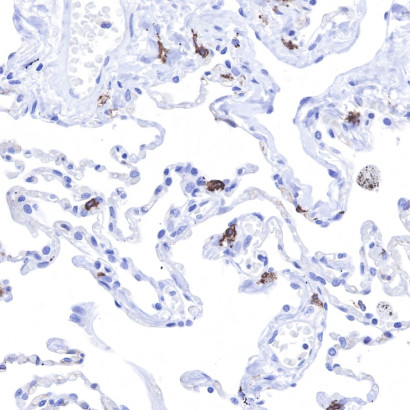

| S0B2084 | S-RMab® CD117 Recombinant Rabbit mAb (SDT-125-51) | Host : Rabbit Conjugation : Unconjugated |